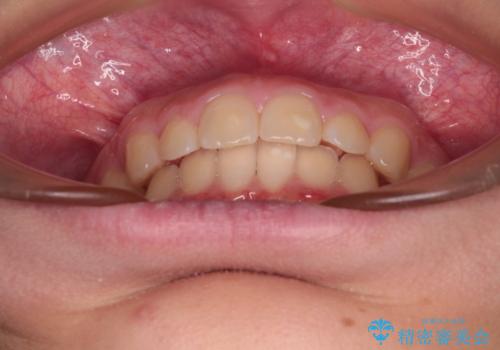

- ヨーロッパにてインビザライン矯正を始めたものの、日本に転居することになり、治療の継続を希望して来院された患者様です。

治療計画に無理がなく、現地担当医と速やかに連絡が取れるとのことで、インビザライン社での転医手続きを行い、継続して治療を行うこととしました。

舌の突出癖により、上下前歯が非接触となっていたため、トレーニングを徹底的に指導し、安定した咬み合わせにより終了させることができました。